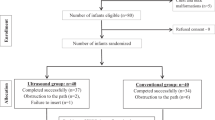

From June 2016 to October 2017, 210 patients were enrolled at a single German center and randomly assigned to undergo PICC implantation under either fluoroscopic control or by means of magnetic tracking and ECG-guided TCS (Fig. 2). Patient characteristics of the two groups were well matched at baseline (mean age 62.3 ± 14.4 years, 134 [63.8%] male, mean BMI 25.7 ± 6.1 kg/m2). Insertion of PICC using TCS took significantly longer compared to fluoroscopy (8.4 ± 3.7 min vs. 5.0 ± 2.7 min, p < 0.001) (Table 1).